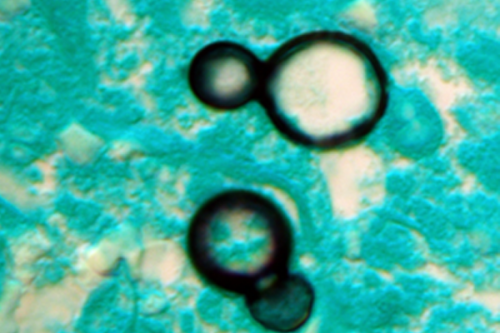

The study, led by scientists at the universities of Manchester in the UK, Amsterdam, and the Westerdijk Institute in the Netherlands, showed that most fungal pathogens identified by the World Health Organisation (WHO) are either already resistant or rapidly acquiring resistance to antifungal drugs.

Aspergillus, Candida, Nakaseomyces glabratus, and Trichophyton indotineae are the major fungicide resistant infections. These can have devastating health impacts on the elderly and people with weak immune systems.